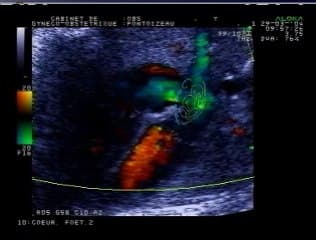

Catherine EGOROFF présente une belle observation riche en séméiologie avec pêle mêle une CIV, un RCIU, un hypospade, un placenta d'aspect anormal. Elle présente cette CIV avec aorte à cheval avec beaucoup de talent didactique en évaluant les différentes options diagnostiques de la cardiopathie.

L'auteur cardiopédiatre fait un point complet du diagnostic à la prise en charge et au pronostic des différentes CIV conotruncales (TOF, APSO, VDDI, Tronc artériel commun), les CIV du septum membraneux et du septum musculaire. Très didactique.